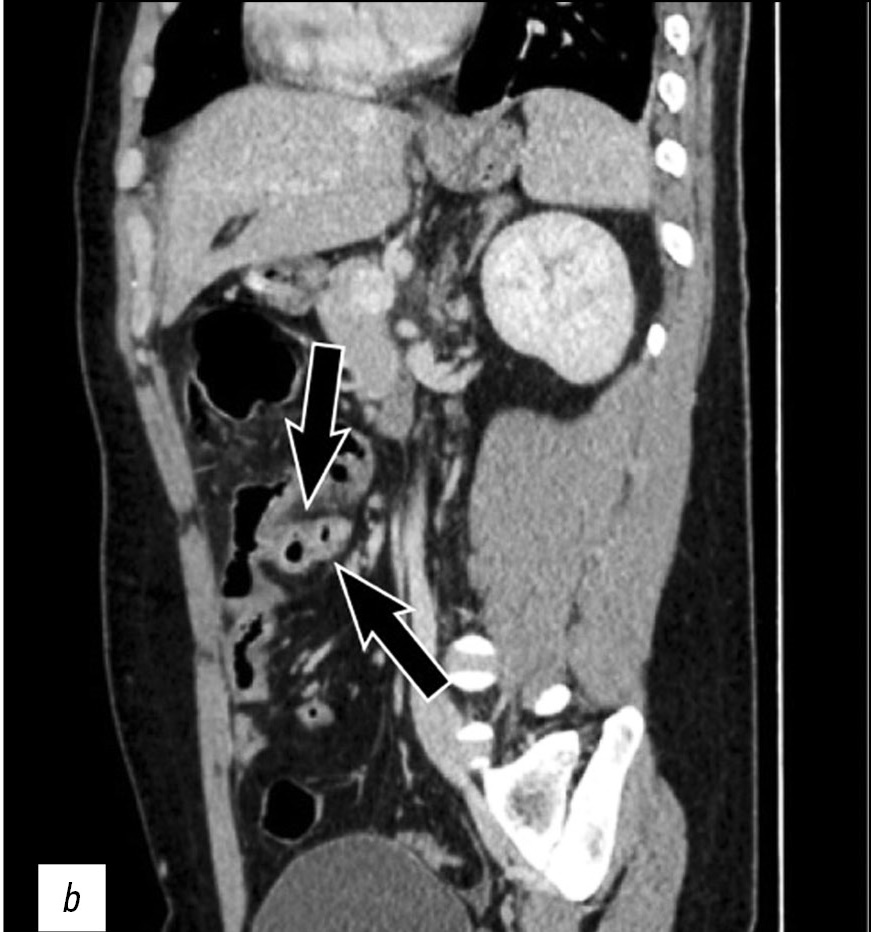

Magnetic resonance imaging radiomics in prostate cancer radiology: what is currently known?

Diagnostic and treatment approaches in prostate cancer rely on a combination of magnetic resonance imaging and histological data.

This study aimed to introduce the basics of the current diagnostic approach in prostate cancer with a focus on texture analysis.

Texture analysis evaluates the relationships between image pixels using mathematical methods, which provide additional information. First-order texture analysis of features can have greater clinical reproducibility than higher-order texture features. Textural features that are extracted from diffusion coefficient maps have shown the greatest clinical relevance. Future research should focus on integrating machine learning methods to facilitate the use of texture analysis in clinical practice.

The development of automated segmentation methods is required to reduce the likelihood of including normal tissue in the area of interest. Texture analysis allows the noninvasive separation of patients into groups in terms of possible treatment options. Currently, few clinical studies reported on the differential diagnosis of clinically significant prostate cancer, including the Gleason and International Society of Urological Pathology grading. Large prospective studies are required to verify the diagnostic potential of textural features.